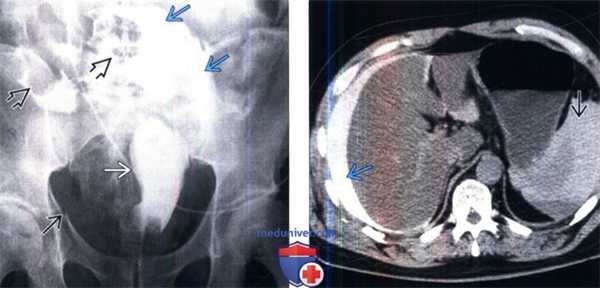

(Слева) Цистография, передняя проекция: определяется смещение мочевого пузыря вследствие наличия гематомы, перелома и внутрибрюшинной экстравазации мочи; обратите внимание на то, что петли кишечника контурируются экстравазатом мочи.

(Справа) КТ без контрастирования, аксиальный срез: у этого же пациента определяется контрастируемая моча в околопеченочном пространстве. Плотность жидкости вокруг селезенки смешанная, вследствие разрыва селезенки с образованием гематомы и смешанного экстравазата с мочой.

(Слева) КТ без контрастирования, аксиальный срез: у этого же пациента визуализируются почки, экскретирующие контрастируемую мочу, вследствие абсорбции контраста из внутрибрюшинной жидкости. Внутрибрюшинное скопление контрастируемой мочи контурируют петли малого кишечника и растягивает карман Морисона.

(Справа) Реконструкция КТ без контрастирования, сагиттальный срез: у этого же пациента определяется спавшийся мочевой пузырь, вследствие наличия катетера Фолея и интраперитонеальной экстравазации мочи, окружающей петли кишечника.